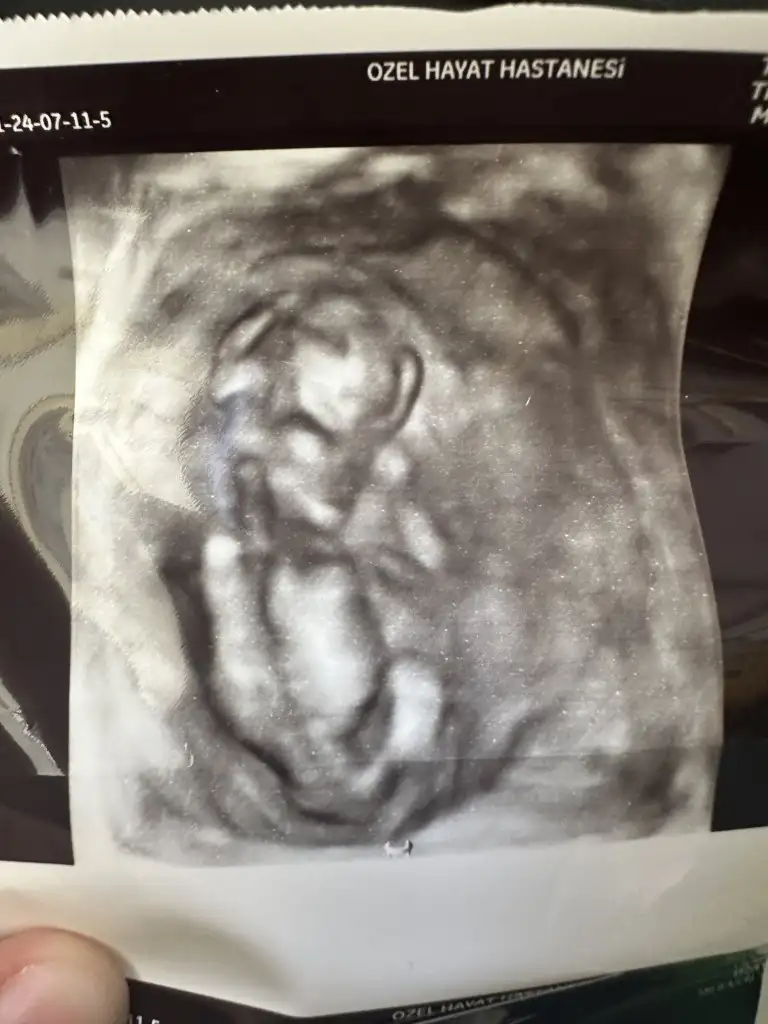

Bana da tahmin yaparmısınız